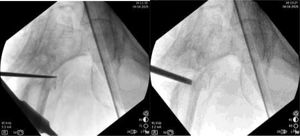

The goal of the surgical technique is to overcorrect the varus deformity to get a final 150° valgus angle at the femoral neck. It is also important that the distal part of the proximal side of the nonunion be in contact with the distal part (diaphyseal bone), to get a dynamic compression from the first postoperative day (Fig. 1).

It is recommended to use a 150° plate for “low” nonunions, and a 135° plate for “high” nonunions (more proximal nonunions). If we use the 150° plate, the cephalic screw should follow the central axis of the femoral neck. Nevertheless, If we use the 135° plate, to get 150° of valgus at the neck, the path for the cephalic screw must be 15° of varus (Fig. 2). The tip of the screw should be as near to the center of the hip as possible. Anyway, a slight downward position of the tip of the screw is possible (as seen in Fig. 1), if necessary, to avoid the same hole as the previous implant.

Lines are drawn as seen in Fig. 2. It is useful to measure the distance of the entry point to de tip of the greater trochanter, or the hole of the previous implant, or any other reference to be seen later on fluoroscopy. That will be the final position in AP view. In the lateral view, the screw should be just in the center.